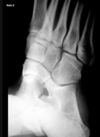

Bico talar

Coalizão calcaneonavicular.